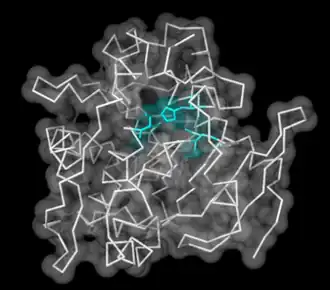

Lingual lipase with catalytic triad highlighted in center | |

Lingual lipase is a member of a family of digestive enzymes called triacylglycerol lipases, EC 3.1.1.3, that use the catalytic triad of aspartate, histidine, and serine to hydrolyze medium and long-chain triglycerides into partial glycerides and free fatty acids. The enzyme, released into the mouth along with the saliva, catalyzes the first reaction in the digestion of dietary lipid, with diglycerides being the primary reaction product.[1] However, due to the unique characteristics of lingual lipase, including a pH optimum 4.5–5.4 and its ability to catalyze reactions without bile salts, the lipolytic activity continues through to the stomach.[2] Enzyme release is signaled by the autonomic nervous system after ingestion, at which time the serous glands under the circumvallate and foliate papillae on the surface of the tongue[3] secrete lingual lipase into the grooves of the papillae, co-localized with fat taste receptors. The hydrolysis of the dietary fats is essential for fat absorption by the small intestine, as long chain triacylglycerides cannot be absorbed, and as much as 30% of fat is hydrolyzed within 1 to 20 minutes of ingestion by lingual lipase alone.[2]